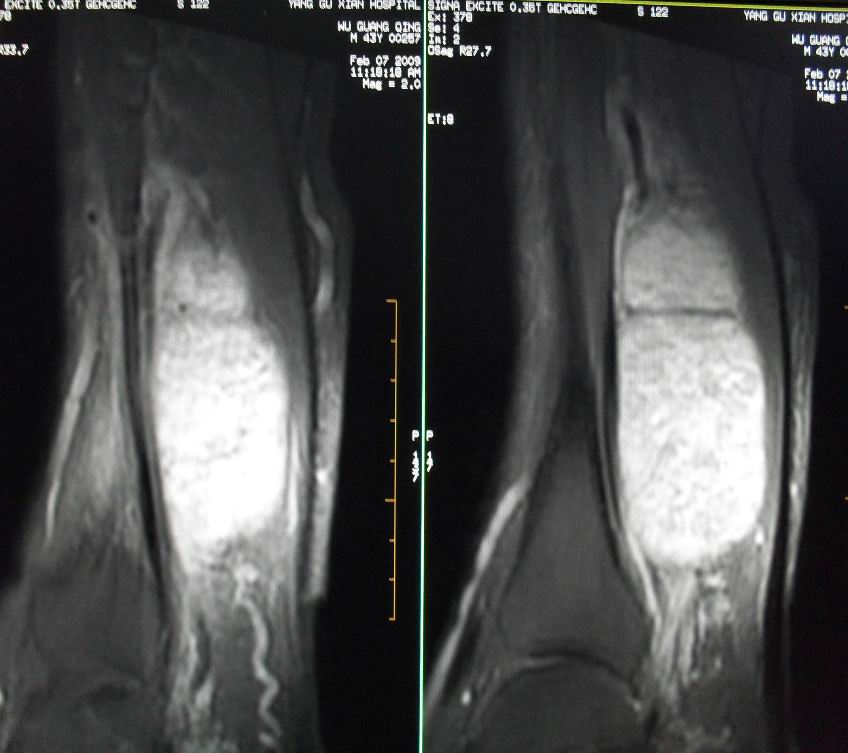

患者男43,右小腿后部软组织肿块2~3年,近期增大明显。平扫加强化。已手术。

1)呈等长t1混杂t2信号,其内见多发类圆形长t1长t2异常信号,病灶主要沿肌间隙生长,但有完整的包膜.gd_dtpa显示:病灶呈明显不均匀的强化,但未见迂曲的强化血管影.

呈等长t1混杂t2信号,其内见多发类圆形长t1长t2异常信号,病灶主要沿肌间隙生长,但有完整的包膜

本病例软组织肿块大,内信号不均匀,有多个囊变区,包膜完整,本片经山东省医学影像研究所mri室王主任会诊术前考虑良性肿瘤,不排除恶变,在北京某医院手术,穿刺及术后病理均为良性,未发现恶变。

本病例软组织肿块大,内信号不均匀,有多个囊变区,包膜完整,本片经山东省医学影像研究所mri室王主任会诊术前考虑良性肿瘤,不排除恶变,在北京某医院手术,穿刺及术后病理均为良性神经鞘瘤,未发现恶变。[face=宋体][/face]

谢谢楼主反馈手术结果!该病灶巨大,但与周围组织分界清晰,其内低密度规整,均支持良性病变。